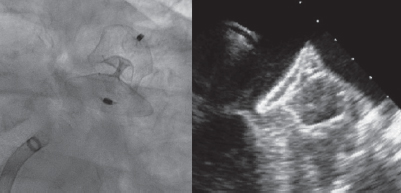

A 28-mm Amulet device was chosen to perform the procedure. A 14-Fr introducer sheath was advanced into the left atrium and, after a selective angiography, the device was deployed inside the LAA in a regular fashion. The first deployment did not achieve a good position (partially outside the appendage) and the device had to be recaptured. A second attempt was made with significant counterclockwise rotation of the sheath that achieved a peculiar “twisted” deployment of the body of the device (figure 2) whose distal part was actually deployed inside the appendage. It was carefully recaptured and after discarding pericardial effusion, it was re-implanted in a good position this time with no further need to change the device (figure 3). A transthoracic echocardiography performed the next day revealed no pericardial effusion. The TEE performed 1 month later revealed no leaks or thrombi on the device either.

Figure 3.